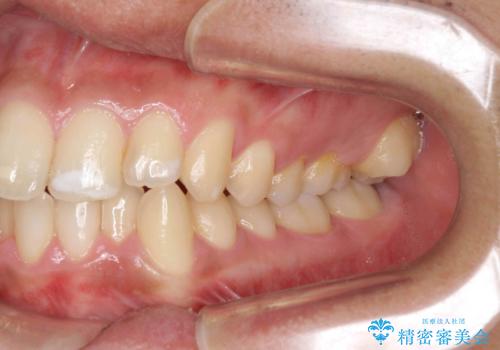

歯を抜かない矯正 奥歯のすれ違い咬合 下の八重歯

- 前歯のガタガタを主訴に来院。

奥歯はすれ違ってしまっていました。

口元も出ておらず、非抜歯を希望されたため、IPR(歯を削る処置)でスペースを確保しました。

上顎両側7番(一番奥の歯)はすれ違っており、虫歯になっていました。